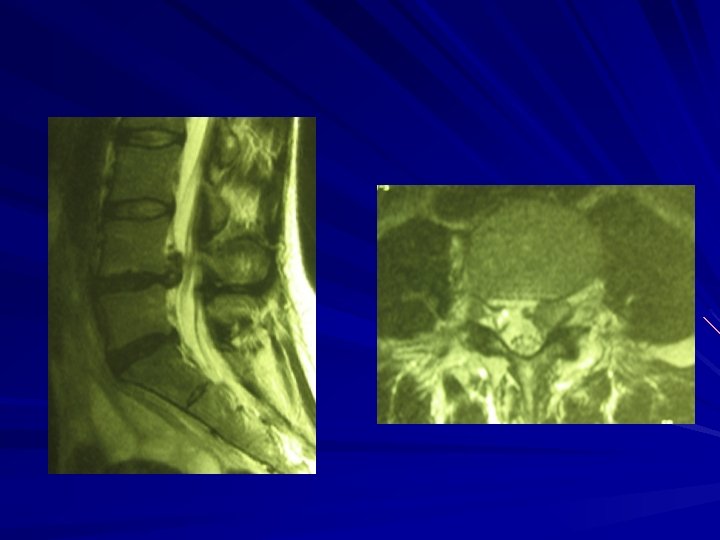

IMPERATIF en cas de sciatique PARALYSANTE Doit rester le dernier recours Sciatique très douloureuse (jour et nuit) et résistante au traitement médical L’Imagerie (Scanner, IRM) doit concorder avec les symptômes HERNIE DISCALE LOMBAIRE CANAL LOMBAIRE ETROIT (Arthrose) AUTRES CAUSES (Neurinomes)

HERNIE DISCALE LOMBAIRE Discectomie micro chirurgicale Discectomie par voie endoscopique Nucléotomie percutanée Nuclétomie percutanée et laser

Canal lombaire étroit Elargissement du canal lombaire Risques et suites idem que pour la hernie discale lombaire Peut être associé à une hernie discale lombaire